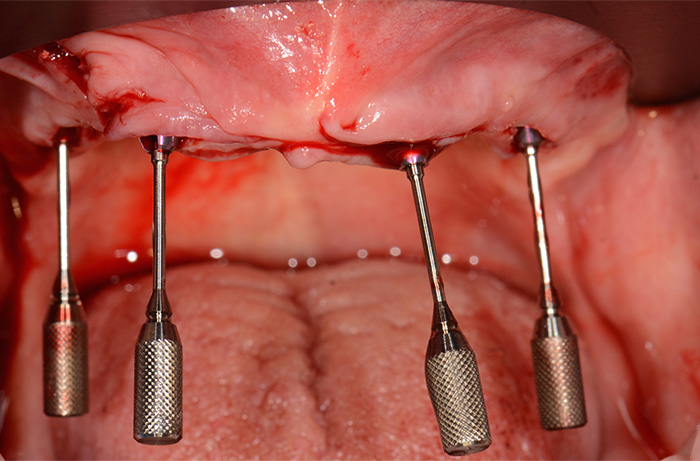

Fig. 7 : Objectivation des axes implantaires après pose de 4 nouveaux piliers coniques SRA (2 droits en hauteur 2.5 et 2 angulés à 30° pour les implants postérieurs).

Fig. 10 : Mise en place des transferts pour piliers coniques.